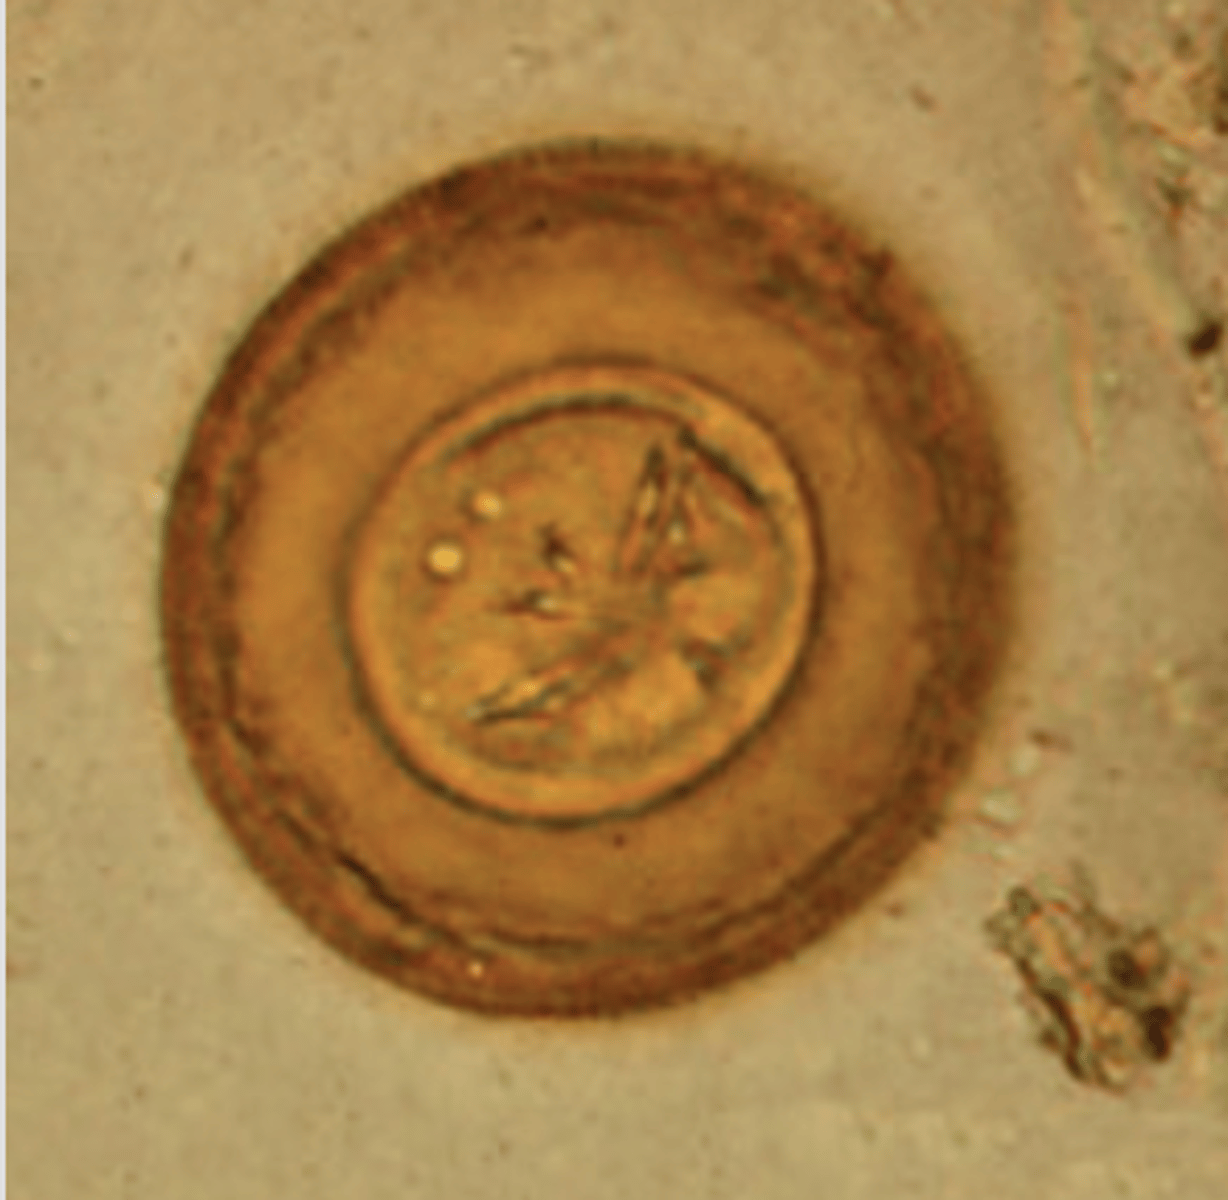

Hymenolepis diminuta